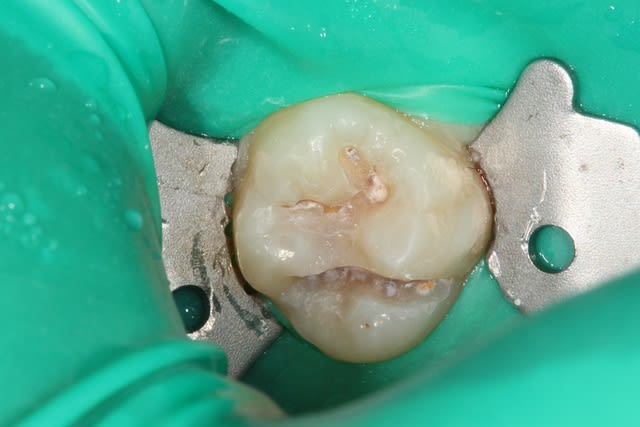

P1020069_njipcn.jpg

Voir le message contenant cette image